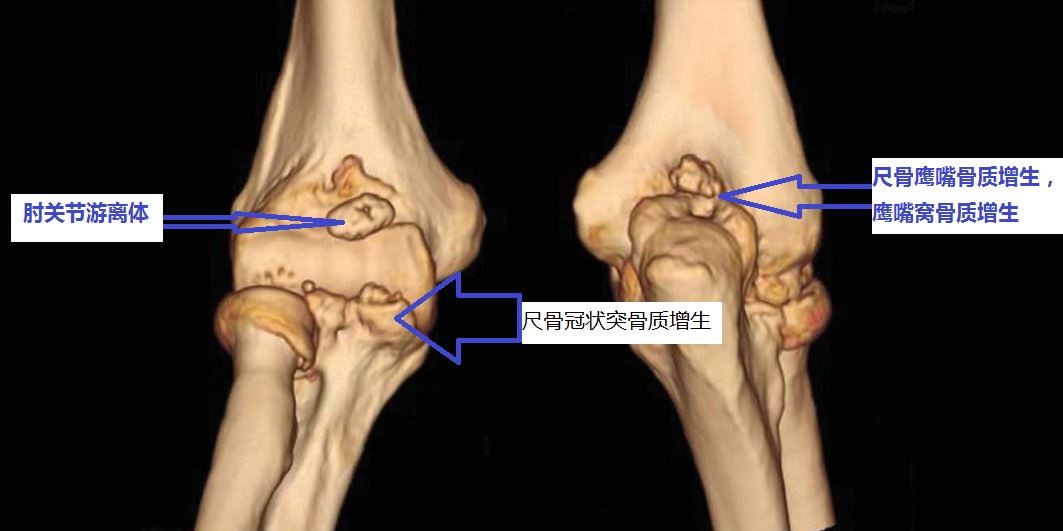

伸不直往往是因为:1、尺骨鹰嘴骨质增生;2、肱骨远端后侧的尺骨鹰嘴窝骨质增生填塞;3、肘关节前侧的关节囊挛缩;4、肘关节内的游离体卡住了;等等。

屈不下来往往是因为:1、尺骨冠状突骨质增生;3、肱骨远端前面的尺骨冠状突窝骨质增生;4、肘关节后侧的关节囊挛缩;等等。